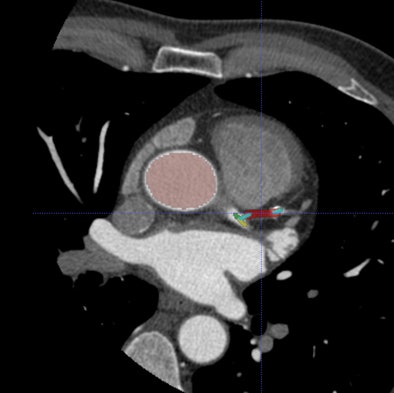

| Axial CT image with overlay coloring. |

The software begins by detecting and segmenting the aorta, and proceeds with the localization of the coronary artery ostia as contrast-filled structures connected to the aorta, Schoepf et al explained. Tubular components are tracked to build the coronary tree, which is then "pruned" of erroneously connected structures.

"The reconstructed coronary artery tree is split into disjoint vessel segments and analysis is performed for each segment separately," the authors wrote. "External boundaries and the lumen of the artery are delineated using an iterative model-based variation approach. Calcified lesions are detected and segmented. Noncalcified plaque is detected as a hypoattenuating area between the external vessel boundary and lumen without calcium."

Parameters are extracted for every cross-section of the vessel segment, including presence and size of plaques, bifurcations, noise level, and extent of artifacts. Finally, the algorithm "matches extracted features to the characteristics of lesions that were used to train the algorithm" and deploys a mark if the lesion features are likely to indicate a significant stenosis, they wrote.